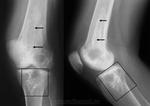

Костномозговые обызвествления обычно наблюдаются в длинных трубчатых костях - в их метафизарных или метадиафизарных отделах. Мы наблюдали их преимущественно в верхних и нижних метафизах, вернее метадиафизах, плечевых и бедренных костей. В единичных случаях встречались обызвествления костного мозга и в нижнем метадиафизе большеберцовой кости.

Рентгеновская картина обызвествлений костного мозга неоднотипна. Чаще она представляется в виде хлопьевидных теней - конгломерата, ограниченного в пределах 3 - 4 - 5 см и более, иногда в виде плотных теней, реже - более мелких вкраплений.

Обызвествления костного мозга не сочетаются с реактивными изменениями со стороны кости. Обычно не наблюдается ни периостальных наслоений, ни склерозирований структуры, остеопороза. Эти обызвествления следует относить к дистрофическому типу, т. е. к обызвествлениям, возникающим на почве дегенеративных изменений тканей. Причина дегенеративных изменений тканей костного мозга с последующими обызвествлениями не всегда ясна. В литературе имеются единичные сообщения, в которых обызвествления костного мозга на основании подходящей локализации и формы трактуются как последствия инфарктов. Можно, конечно, допустить такой генез обызвествления: последние возникают на почве некротических изменений, которые являются последствиями инфарктов. Но в практике при несомненных инфарктах, например при кессонной болезни, мы не наблюдали обызвествлений костного мозга. Костные инфаркты проявляются также выраженными деструктивными изменениями типичного вида, чего не отмечается при обызвествлениях костного мозга.

Вообще кровоизлияния в тканях очень часто приводят к обызвествлениям. Однако мало оснований считать обызвествления костного мозга последствиями кровоизлияний уже потому, что мы их почти не встречаем при определенных травматических повреждениях, например при переломах, прободениях метафизов гвоздем при скелетных вытяжениях, огнестрельных ранениях, непосредственных ушибах кости, при которых возникновение кровоизлияний в костном мозгу более чем вероятно. Только однажды мы наблюдали крупное (4 х 7 см) обызвествление костного мозга в нижнем метафизе бедренной кости, связанное с ее переломом (рис. 194).

Рис. 194. Обызвествление костного мозга в нижнем метафизе бедренной кости, связанное с переломом.

Больная 50 лет много лет страдает артритом правого коленного сустава, хромает. Имеется атрофия мускулатуры конечности, ограничение подвижности в коленном суставе. Несколько лет назад был перелом бедренной кости.

Рентгенограмма: кости сустава порозны; суставная щель значительно сужена; суставные края костей сустава узурированы; на границе средней и нижней трети бедренной кости следы сросшегося со смещением под углом перелома; в нижнем метафизе кости конгломерат известковых отложений; виден след продольной трещины кости, подходящий к метафизу.

В данном наблюдении обызвествление костного мозга, безусловно, можно связывать с кровоизлиянием, вызванным переломом. Но следует принять во внимание и некоторые биологические особенности - давнее костно-суставное заболевание, остеопороз, - возможно, способствующие обызвествлению гематомы в костном мозгу. Логичнее всего считать наблюдаемые обызвествления костного мозга как последствия некротических асептических процессов в костном мозгу, возникающих в результате рефлекторных расстройств кровообращения в сосудах последнего. Нужно также учитывать индивидуальные особенности организма, возможность расстройства трофики тканей.

Распознавание обызвествлений костного мозга не представляет затруднений. Оно основывается главным образом на характерной картине и определенной локализации. При рентгенологическом исследовании легко определяются тени, расположенные внутри кости (в костно-мозговом пространстве), характерные для известковых отложений. Они бесформенные, в виде хлопьевидных инкрустаций, плотные. Отсутствие костной структуры отличает их от гетерогенных окостенений.

В ряде случаев тени обызвествлений костного мозга настолько характерны, что исключают дифференциацию. Тем не менее при распознавании обызвествлений костного мозга следует принимать во внимание и другие внутрикостные обызвествления, например во внутрикостно расположенных хондромах (энхондромах), в изолированном обызвествленном туберкулезном очаге (3. А. Лебедева), а также изолированные уплотнения костной структуры - крупные солитарные компактные, островки. Часто в хондромах возникают дегенеративные процессы, приводящие к кистозным образованиям, обызвествлениям и окостенениям. Обызвествления в хондромах бывают преимущественно частичными, чередующимися с участками хряща, что рентгенологически представляется просветлениями наряду с тенями известковых отложений. При энхондромах часто имеются и костные изменения утолщения кости, деформации кортикального слоя в виде истончения, выпячивания. На основании этих признаков нетрудно отличить обызвествления в хондромах от таковых костного мозга.

Инфаркт костного мозга.

Бывает, вот только "фейс" отличается.

На представленных рентгенограммах паттерн действительного не "инфарктный", но спорить можно долго, а правду узнаем только выполнив МРТ или РКТ.

Визуально процесс проявляется обызвестлением, о чем свидетельствуют и приведенные Вами же сканы.

Мое утверждение касалось принципиальной возможности обызвестления костного мозга, в частности при инфаркте. Я не настаивал и не настаиваю, что автором поста на рентгенограммах представлен инфаркт мозга/кости, а чем уже говорил.

Возможности КТ и МРТ в диагностике данного дифряда широко известны и как безвредный метод исследования можно рекомендовать МРТ нижней трети бедра.